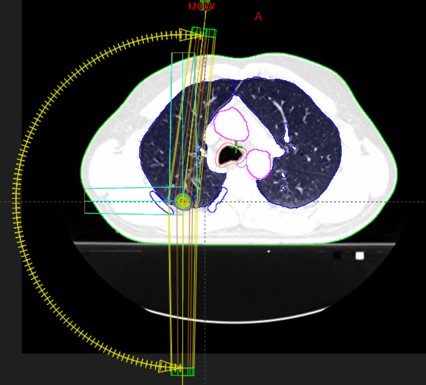

SABR meta pulm. dex. (07.06.-16.06.2017.)

SABR meta pulm. sin. (27.01.-03.02.2023.)